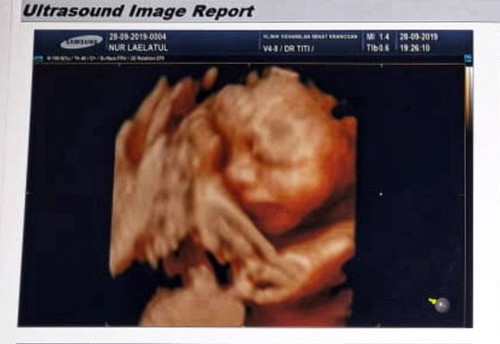

hpl desember akhir tahun baru mana suaranya bund?

Sudah merasakan apa aja nih bund #usg27weeks #babyboy